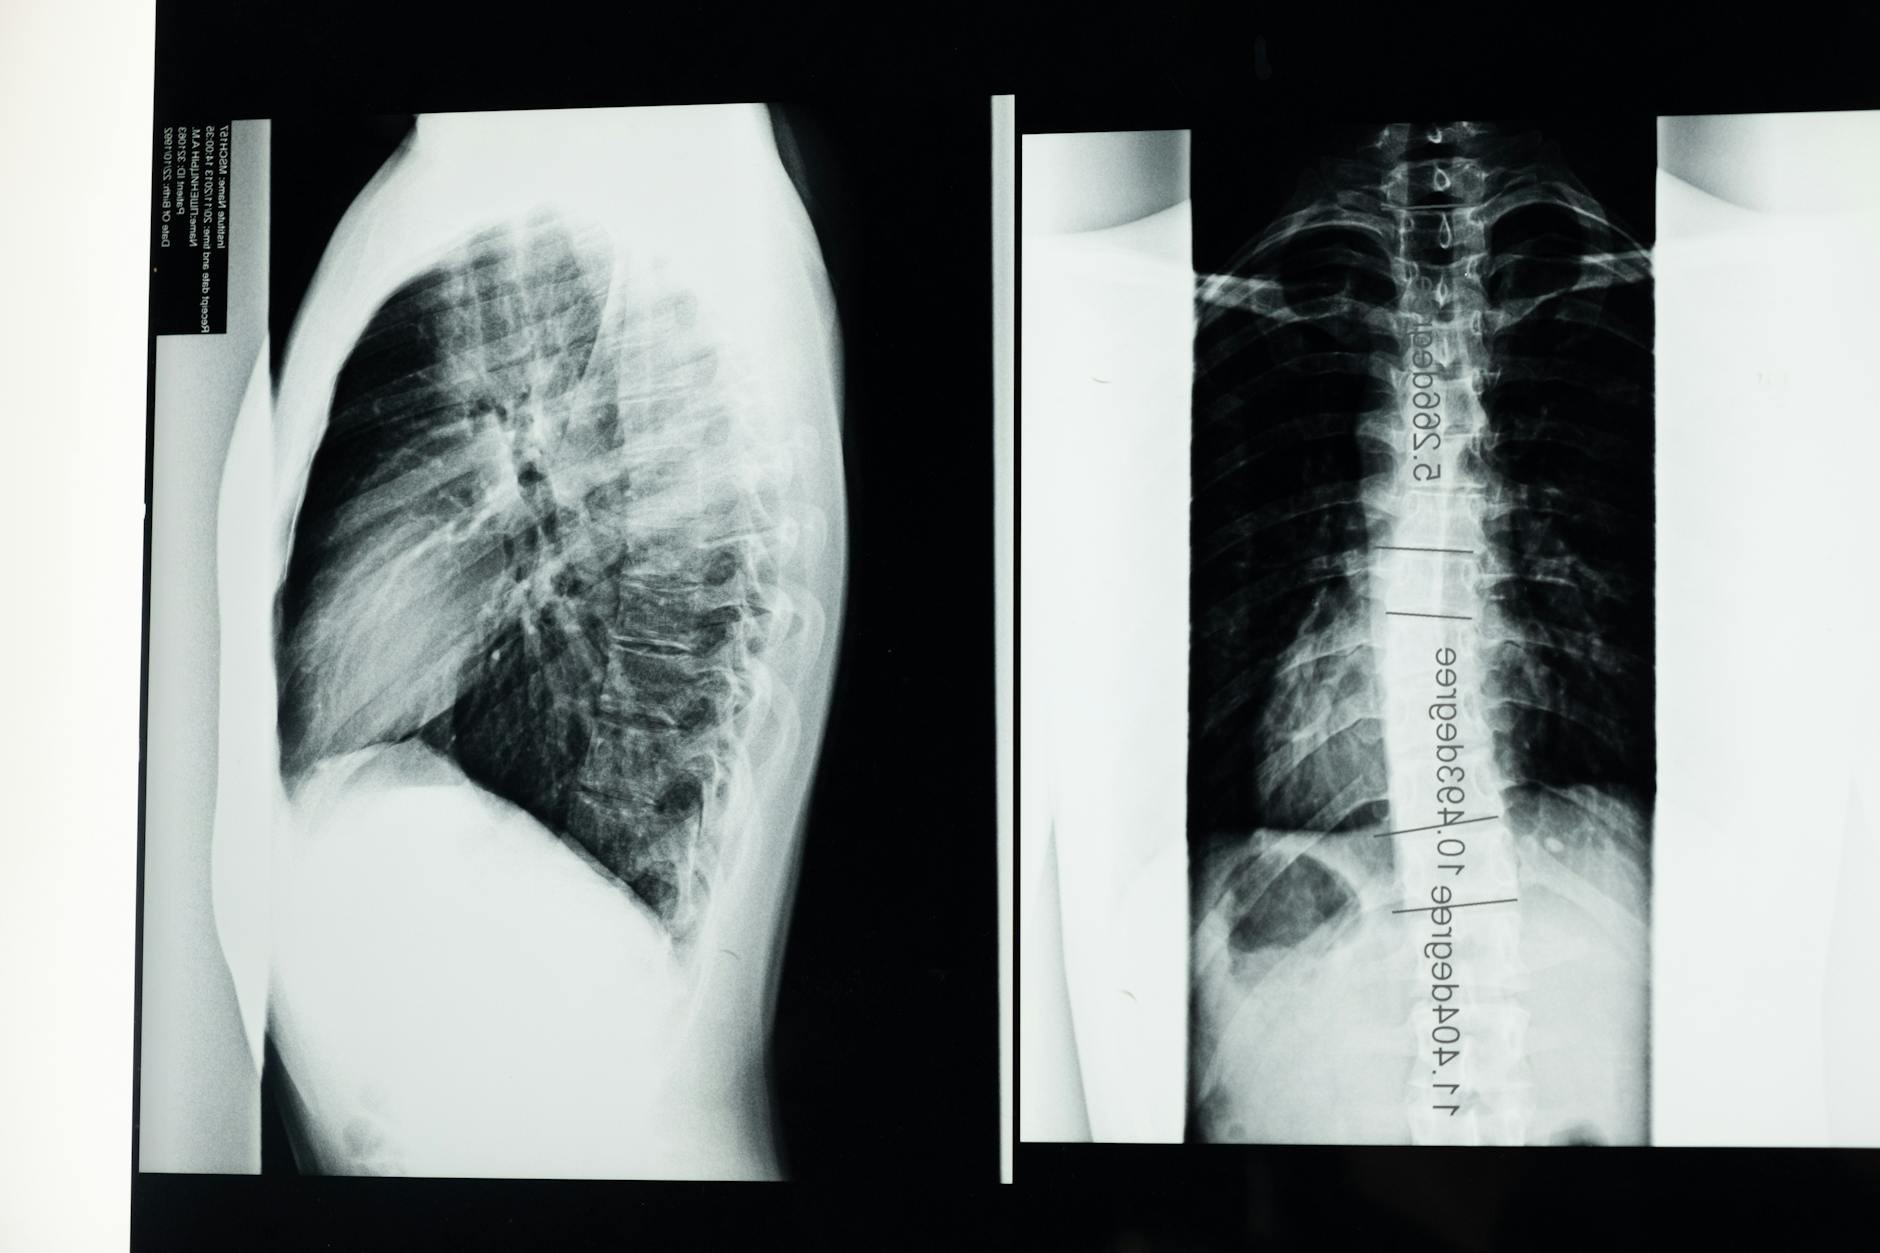

Poród to szereg kolejno następujących procesów w wyniku których rodzi się dziecko. Poród dokonywany jest w wyniku skurczów mięśnia macicy, przepony oraz mięśni ściany brzucha. Poród dzieli się na okresy, pierwszy to okres między początkiem bolesnych skurczów a pełnym rozwarciem szyjki macicy, drugi okres porodu kończy się urodzeniem dziecka , trzeci okres porodu to wydalenie łożyska i błon płodowych. Około 38 tygodnia ciąży płód jest wystarczająco dojrzały, aby opuścić organizm matki i rozpocząć samodzielne życie. Kiedy macica przygotowana jest do wystąpienia akcji skurczowej. Symptomy zbliżającego się porodu, to: obniżenie dna macicy, częste skurcze macicy, odejście krwistego czopu śluzowego, dojrzewanie szyjki macicy. Poród naturalny to taki, który przebiega siłami i drogami natury, w pozycji, jaką wybiera kobieta. W taki poród medycyna nie ingeruje. Ingerencja to nie tylko cesarskie cięcie, ale również podanie oksytocyny, przebicie pęcherza płodowego, masaż szyjki macicy, czy układanie rodzącej na wznak w decydującym momencie wydawania dziecka na świat. Poród kleszczowy , to taki w którym wspomaga się wydobycie dziecka przy pomocy kleszczy położniczych w stanie pełnego rozwarcia szyjki macicy.Poród pośladkowy w którym częścią przodująca są pośladki dziecka jest niebezpieczny zarówno dla matki i dziecka, czasami jednak zdarza się że dziecko samo z siebie w ostatniej chwili obróci się do pożądanej pozycji. Pośladkowe ułożenie dziecka szczególnie w sytuacji gdy jest ono dość duże jest wskazaniem do wykonania cesarskiego cięcia.